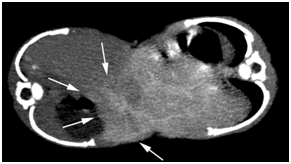

In the early phase, the anatomy of the arterial vasculature was delineated clearly. Due to rapid blood circulation, the portal vein was also demonstrated. In Twin A, the celiac trunk and superior mesenteric artery branched off the abdominal aorta in the proper order (Figure 2). No blood flow from Twin A’s superior mesenteric artery was observed in Twin B, ruling out small intestinal conjunction. The proper anatomy of the branches of the celiac artery and portal vein in Twin A was confirmed. The fused lobe of the liver in Twin B showed an enhanced portal vein that communicated with that of Twin A (Figure 3). In Twin B, the fused lobe was enhanced secondary to crossover circulation in the delayed phase (Figure 4). The fusion area was seen as an irregular strip. No definite enhancement in the other area of liver in Twin B was seen. The entire liver of Twin A was enhanced.

Figure 3 Axial MPVR image of early-phase CT shows portal venous communication with the other baby (arrows).

Figure 4 Axial MPVR image of delayed-phase CT shows that the fused lobe of the liver in Twin B was enhanced secondary to crossover circulation in the delayed phase (arrows).